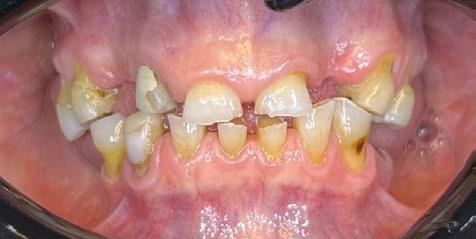

Exploración Intraoral

Presenta un estado oral deficitario. Parcialmente edéntula, con colapso de mordida, migración dental patológica, restauraciones de resina antiguas fisuradas y filtradas, transparencia y exposición de cámara pulpar secundaria a desgastes con pérdida de estructura e integridad de tejido dental importante (Figuras 1 a 4). Portadora a tiempo parcial de prótesis removibles desadaptadas de más de 10 años de antigüedad, refiriendo incapacidad de adaptación a este tipo de prótesis.

Ramos-Ríos y cols. estudiaron dos escuelas con niños de rango de edad de 6 y 12 años, en México. Para ello, se empleó un cuestionario para los padres y se obtuvo que un 6,84% padecían asma; de éstos se llevó a cabo el estudio (Tabla 1).

Tras los resultados obtenidos llegaron a la conclusión de que son muchas las patologías asociadas al asma, y no solo repercusiones sobre su salud oral, sino maloclusiones del tipo mordida abierta o paladar ojival asociadas a deglución atípica, propias de una respiración oral

también relacionada con esta patología. El pH ácido se encontró en un 96,42% de los niños y se sabe que tiene relación directa con la formación de caries. No encontraron asociaciones con xerostomía, erosión dental o candidiasis, siendo estas patologías relacionadas, al mismo tiempo, con la inmunosupresión generada por los fármacos (1).

Domenzain-Sanchez y cols. realizaron un estudio transversal de casos y controles con pacientes de 5 a 12 años. Un 80% de los asmáticos presentaban caries, a pesar de que los autores no encontraban relación directa entre caries y enfermedad asmática. Éstos consideran que la medicación es la causa principal de las caries, ya que gran parte se queda en la orofaringe, además de reducir el flujo salival y tener azú cares. Los niños asmáticos tienen 1,02 mayor riesgo de erosión dental que los niños no asmáticos; esto se debe a la acidez de los fármacos que reducen el pH y provocan reflujo gastroesofágico. La mayoría de los estudios no avalan una asociación directa con el bruxismo, ya que en niños es muy frecuente, pero concretamente

en este estudio resultó que un 14% presentaban bruxismo dentro del grupo de asmáticos y lo justifican con la obstrucción parcial prolongada o completa de las vías respiratorias (53).

Gorji y cols. realizaron un metaanálisis para establecer la asociación entre caries y asma. Llegaron a la conclusión de que el asma es un factor de riesgo de caries y de no tratarse adecuadamente y tener las medidas preventivas necesarias, aumenta la probabilidad de desarrollar caries. Atendiendo a la falta de suministro de oxígeno, los ameloblastos se ven afectados y se altera la formación del esmalte, lo que origina defectos sin posibilidad de reparación como el MIH o síndrome de hipomineralización incisivo-molar (9).

La respiración bucal es muy frecuente en niños con asma y surge como una función adaptativa, ya que tienen dificultad respiratoria. Puede implicar cambios de postura a nivel cervical, afectando al crecimiento del niño; además de alteraciones en el crecimiento de maxilares y en los m ú sculos orofaciales, la posición baja de la lengua detiene el crecimiento transversal, originando paladar ojival y mordida cruzada posterior. A nivel anterior, la alteración en la posición lingual provoca deglución atípica.

Castañeda-Zetina y cols. realizaron un estudio para comparar las maloclusiones en niños asmáticos y sanos, en el cual se incluyeron 186 pacientes de entre 5 y 12 años. Los resultados obtenidos fueron que más del 50% de los niños asmáticos tienen respiración oral. Las principales alteraciones oclusales presentadas eran mordida abierta anterior y mordida cruzada posterior, menos frecuente; además de una menor frecuencia de clase III, solo un 11,6%, ya que el cambio postural de estos pacientes favorece la entrada del aire inclinando la cabeza hacia atrás y favoreciendo la aparición de clase II al posterorrotar la mandíbula. Estas modificaciones posturales van a producir alteraciones maxilares y desequilibrio en los m ú sculos periorales; por ello, su detección precoz ayudará a resolver el problema con un abordaje multidisciplinario y dando armonía al complejo dentoesquelético (56).